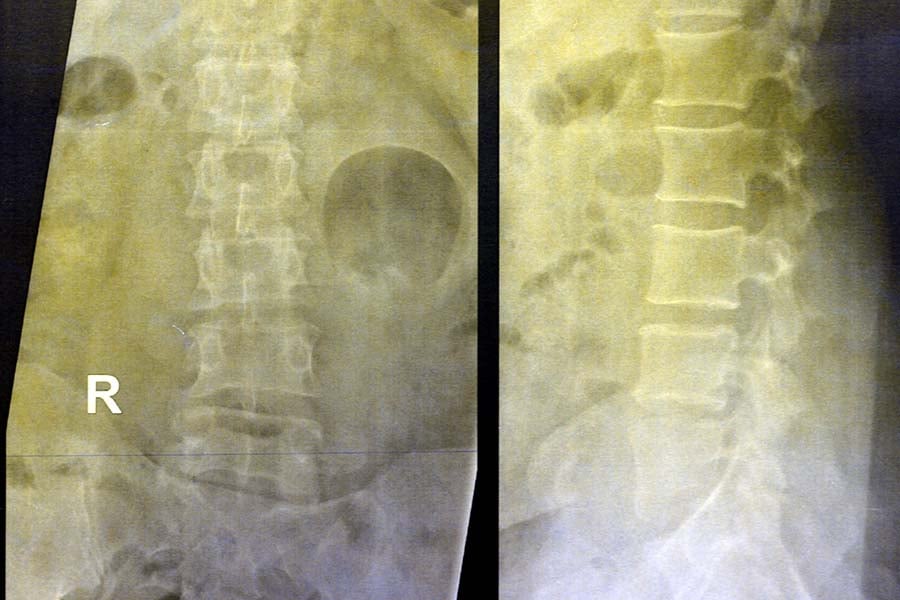

- Рентгенография. Това е стандартно образно изследване, което се извършва за оценка на костни аномалии. Може да разкрие характерните за остеосарком костна деструкция, анормален костен растеж или области на костна минерализация.